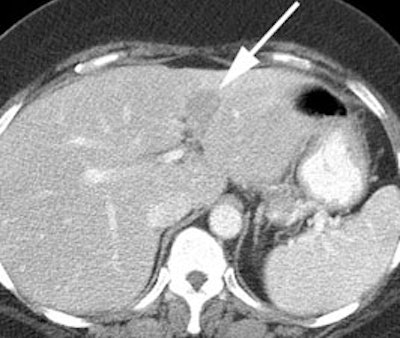

Rising CEA level: The patient below had a history of treated colorectal carcinoma and a rising CEA level. The FDG PET exam demonstrated foci of abnormal tracer uptake in the liver and pelvis (black arrows). Subtle abnormalities could be identified on the CT exam and subsequent surgical exploration confirmed the presence of metastatic disease (white arrows). |